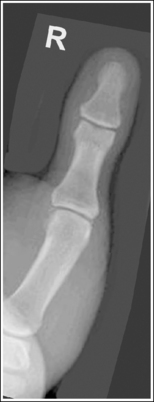

The thumb demonstrates a lateral projection. The anterior aspect of the proximal phalanx and metacarpal demonstrates midshaft concavity, and the posterior aspect of the proximal phalanx and metacarpal demonstrates slight convexity.

• To accomplish a lateral thumb projection, place the patient's hand flat against the IR; then flex the hand and fingers only until the thumb naturally rolls into a lateral projection (Figure 4-18). Overflexion causes superimposition of the second and third proximal metacarpals onto the proximal first metacarpal, obscuring it (see Image 14). When the hand and fingers are accurately flexed and the thumb is in a lateral projection, the midshaft of the proximal phalanx and metacarpal demonstrates concavity on their anterior aspects and convexity on their posterior aspects. If the patient's hand is not rotated enough to place the thumb in a lateral projection, the posterior aspects of these midshafts show some degree of concavity (see Image 15).